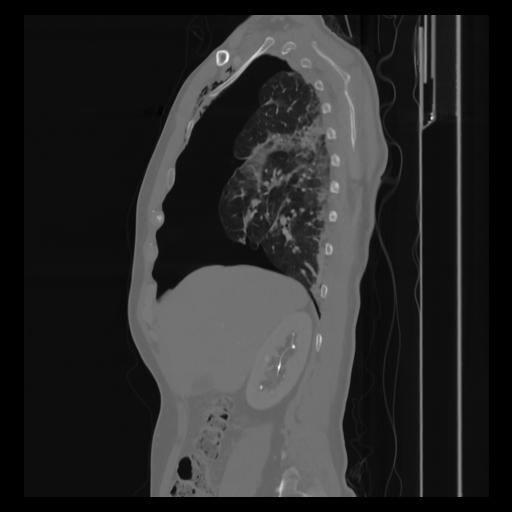

30 CUERPO,CE,Sagittal,3.000,CUERPO,Sagittal,